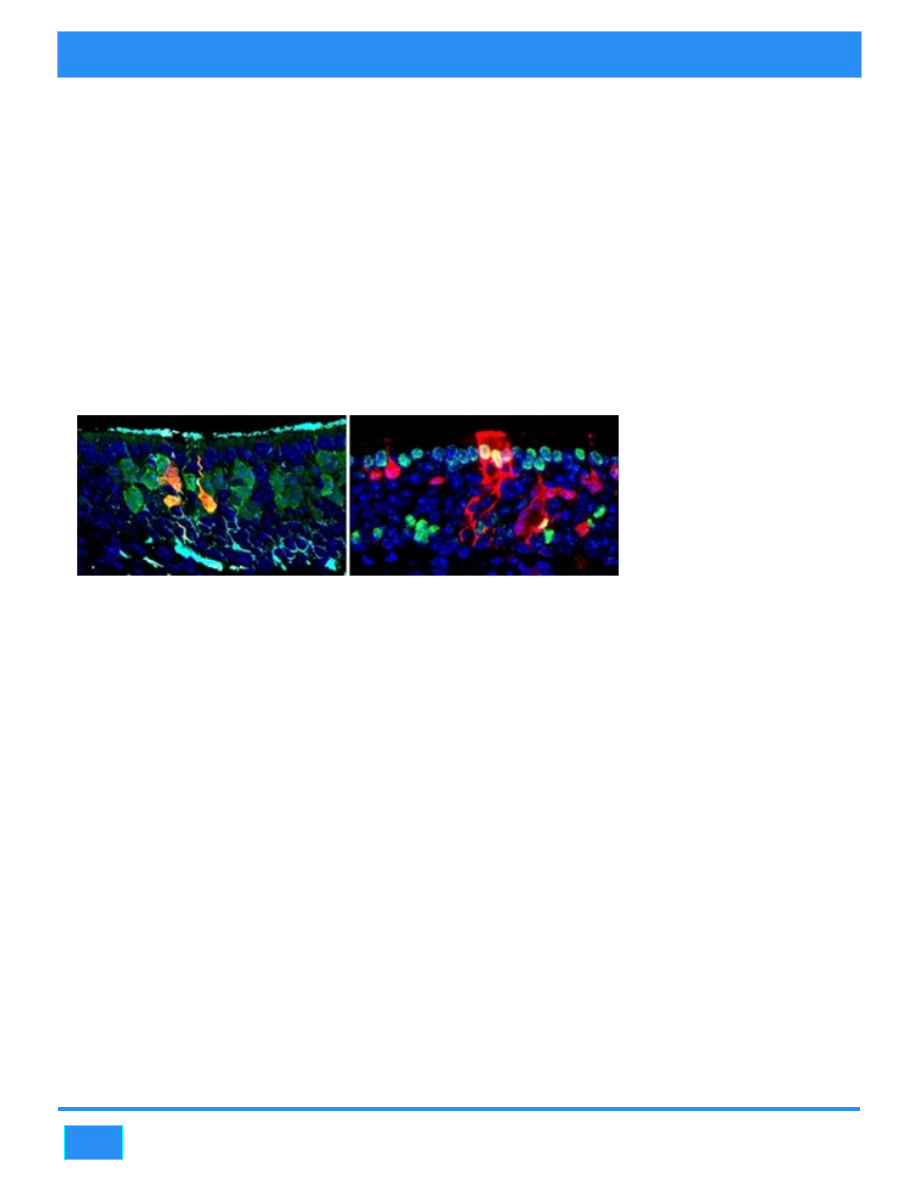

Stem cells are undifferentiated, or unspecialized; they are highly potent and able to generate many

different types of cells. Researchers at Tufts University School of Medicine, led by Dr. James E.

Schwob, are examining the behavior of adult stem cells within the context of aging and, specifically,

the sense of smell. As part of the normal aging process, older adults frequently experience a decline in

The focus of the

research at Tufts is on

e n l a r g i n g t h e

population of adult

s t e m c e l l s t h a t

maintain the sense of

s m e l l i n y o u n g

adults, but which

d e t e r i o r a t e w i t h

aging. The ultimate

goal is to identify a pharmaceutical preparation that has that effect. In a study published in the issue of

Cell Stem Cell, the researchers provide the first evidence that it is possible to regenerate stem cells of

the nasal tissue in mice, thus enlarging the population of adult stem cells. The team took advantage of

that natural healing process. Adult stem cells regenerated in mice with injured nasal tissue. When

those adult stem cells were transplanted into other mice, they were able to regenerate all the different

cell types in the nasal tissue, also called the olfactory epithelium. This expansion of the stem cell

population improved when the researchers swabbed a pharmaceutical preparation into the nose; the

drug combination pushed progenitor cells to remain upstream as adult stem cells.

Though the response involved the now-famous Yamanaka factors, the strategy developed by Schwob

and his team is more efficient and less complicated than the induced pluripotent stem cell (iPSC)

Nobel Prize-winning approach developed by Dr. Shinya Yamanaka. Yamanaka's approach was

designed to replace stem cells lost to aging by inducing cells taken from adult tissues to behave like

embryonic stem cells, by forcing them to express four genes that are usually expressed in embryonic

stem cells.

The research team from Tufts determined that only two of the four factors used by Yamanaka to

artificially reprogram adult cells into iPSCs are critical to the process of pushing the olfactory cells to

become more stem cell-like. "We are the first researchers to gain insight into the molecular

mechanism responsible for allowing these adult progenitor cells to become more potent.”If we can

restore the population of stem cells in the olfactory epithelium by regenerating them or by

administering the right drug as a nasal spray, we may be able to prevent deterioration in the sense of

smell," he continued.